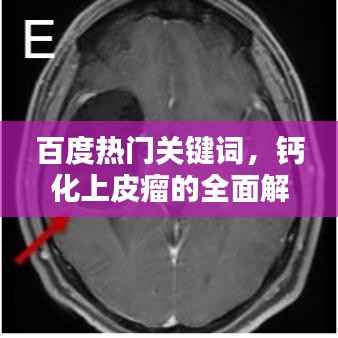

当我们谈论“钙化上皮瘤”这一医学名词时,许多人可能会感到陌生和困惑,本文将通过“百度一下”的方式,带您全面了解钙化上皮瘤,包括其定义、成因、症状、诊断以及治疗方法。

钙化上皮瘤,也被称为皮肤钙化瘤,是一种皮肤良性肿瘤,这种肿瘤主要由过度增生的上皮细胞和钙盐沉积组成,大多数情况下,它们是良性的,不会对身体造成严重影响,它们可能会在皮肤表面形成硬质结节,有时会引发疼痛或不适。

钙化上皮瘤的症状主要包括皮肤表面的硬质结节,可能伴有疼痛或瘙痒,这些结节可能单独出现,也可能成簇出现,它们可能在不同年龄阶段出现,但通常在成年后才会被发现。

诊断钙化上皮瘤

如果您怀疑自己可能患有钙化上皮瘤,最好寻求专业医生的帮助,医生会通过观察皮肤结节的外观、触摸其质地以及询问您的病史来进行初步诊断,在某些情况下,可能需要进行皮肤活检以确诊。